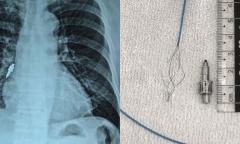

Các bác sĩ cảnh báo tai biến sau thủ thuật làm răng từ việc gắp dị vật phế quản từ dụng cụ nha khoa cho cụ ông 78 tuổi.